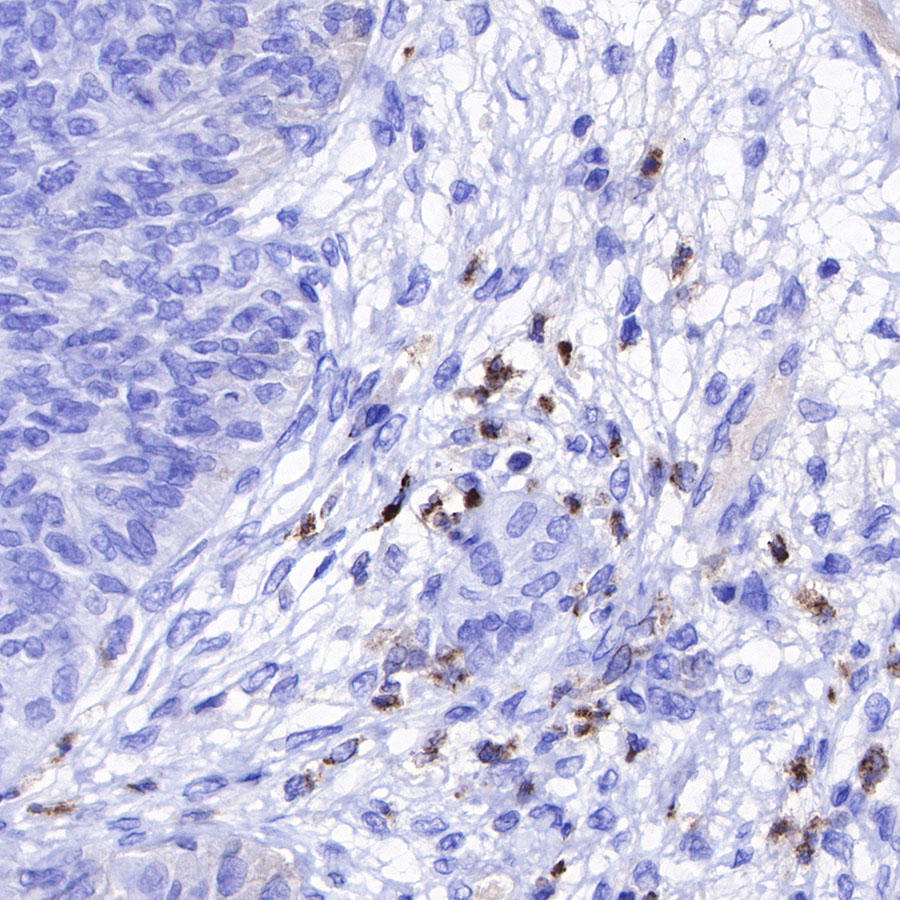

Immunohistochemistry

IHC shows positive staining in paraffin-embedded human tonsil. Anti-Lysozyme antibody was used at 1/100 dilution, followed by a HRP Polymer for Mouse & Rabbit IgG (ready to use). Counterstained with hematoxylin. Heat mediated antigen retrieval with Tris/EDTA buffer pH9.0 was performed before commencing with IHC staining protocol.